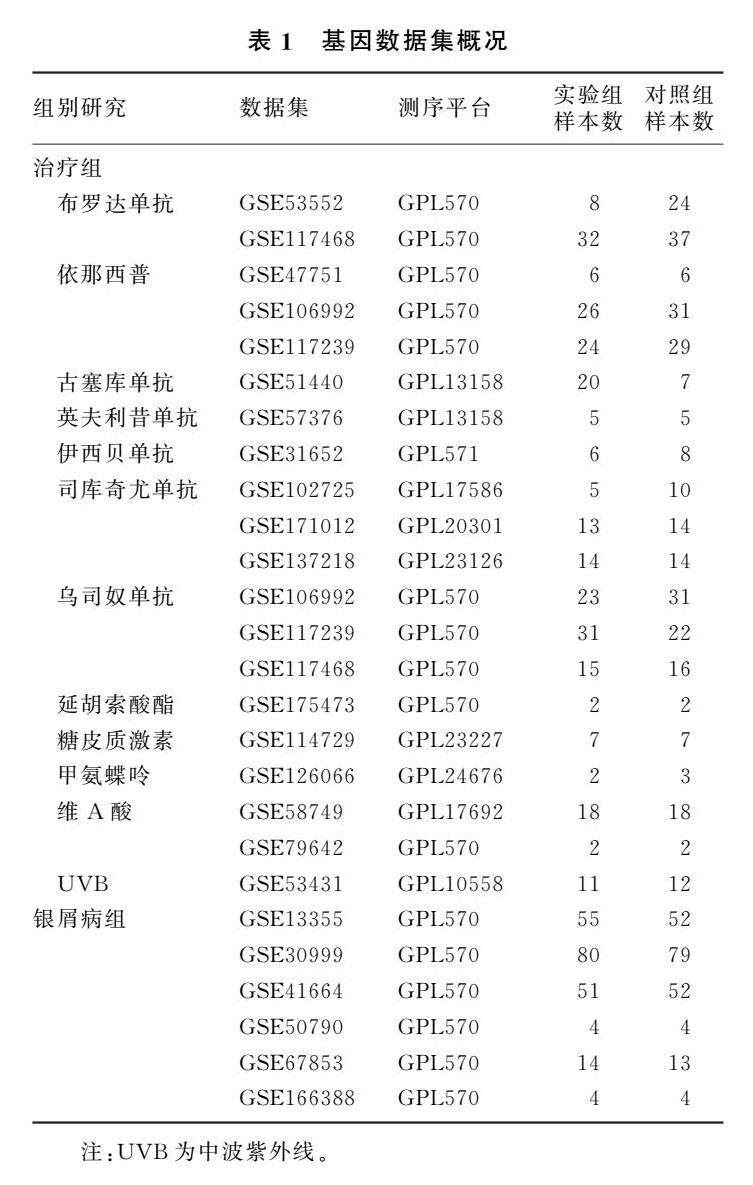

论著 | 不同疗法对银屑病基因表达影响的生物信息学分析

论著 | 不同疗法对银屑病基因表达影响的生物信息学分析